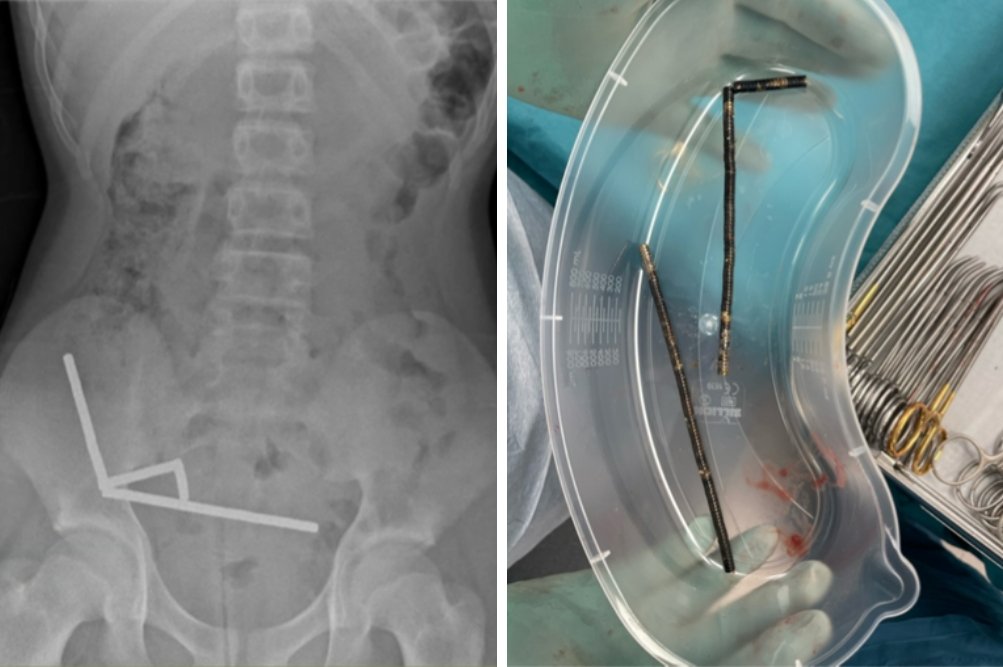

Na levi je rentgenska slika trebuha s štirimi verižnimi nizi magnetov v desnem spodnjem delu trebuha, na desni pa približno 80 do 100 močnih magnetov, odstranjenih med operacijo.

Zdravniki so ugotovili, da so se magneti v njegovih prebavilih spojili in oblikovali štiri verige, kar je povzročilo poškodbe črevesja. Kirurgi so med operacijo odstranili magnete in morali odstraniti tudi dele poškodovanega črevesja.

Prva slika s puščico kaže na dva dela črevesja, zlepljena zaradi magnetov. Druga slika prikazuje krog, ki označuje del slepega črevesa, kjer je zaradi pritiska prišlo do odmrtja tkiva, puščica pa kaže na verigo magnetov v spodnjem delu tankega črevesa.